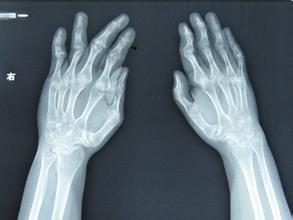

(图:X线下叶女士双手示意图)

体格检查:双手手指变形严重,双腕,双肘肿胀压痛,左肩关节不能上举,压痛明显,双膝关节肿胀,膝关节伸不直,下肢肌肉萎缩,不能站立。

辅助检验:血沉 85mm/h ,血小板 531 ×109/L 。诊断为类风湿性关节炎。